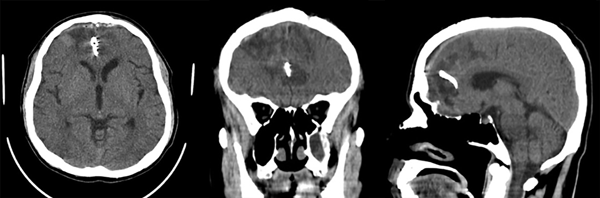

Posteriormente es trasladado a terapia intensiva intubado donde se mantiene bajo sedoanalgesia en infusión por 24 horas y, tras reversión, se evidencia Glasgow 11/15 (respuesta verbal: 4, respuesta motora: 6), sin déficit neurológico aparente. Se retira drenaje subcutáneo a las 48 horas postoperatorias. Se indica tomografía cerebral simple (Figura 3) con buen control de evacuación de las colecciones hemáticas, y la AngioTC con correcta exclusión del aneurisma (Figura 4). El paciente tiene una óptima evolución.

Figura 3. Tomografía cerebral simple. En cortes axial, coronal y sagital se muestra: cuerpo hiperdenso en fisura interhemisférica que genera discreto efecto Hounsfield correspondiente con clip simple de palas rectas normoposicionado. Áreas de encefalomalacia bifrontal. Cisternas de la base libres y permeables, sistema ventricular de topografía normal, preservación de los elementos de la línea media, presencia de surcos y circunvoluciones, adecuada diferenciación sustancia gris-blanca y corticosubcortical. Defecto de craneotomía.